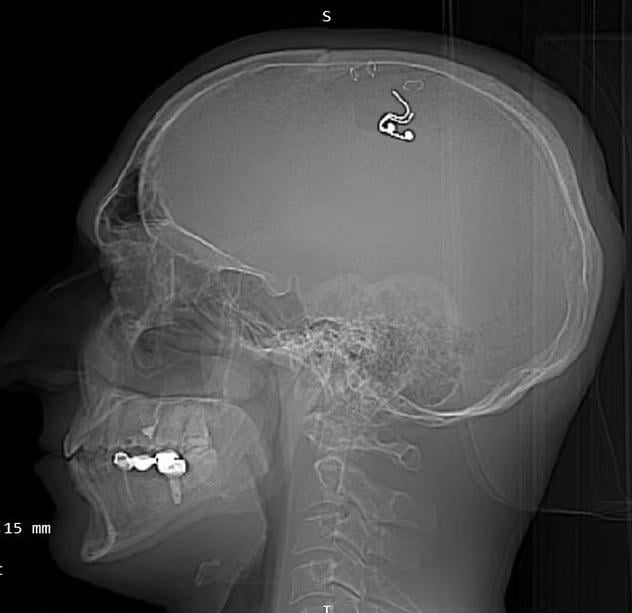

英國《每日郵報》報道,40歲的拉杜加(Michael Raduga)希望像《潛行凶間》所說的那樣,可透過電極改變夢境,上月,他在哈薩克家裡自己進行腦部手術植入晶片,失血超過1公升。拉杜加沒有神經外科醫生資格,從照片可見,他用萬字夾夾住皮膚,用電鑽在頭骨頂部鑽開一個小孔,將由鉑金屬和矽製成的電極植入腦部。之後,他便使用電源刺激腦部製造夢境。

拉杜加自己開腦在頭頂植入晶片,希望像《潛行凶間》的主角能控制夢境。(互聯網)

拉杜加自己開腦在頭頂植入晶片,希望像《潛行凶間》的主角能控制夢境,結果失掉1公升血。(互聯網)